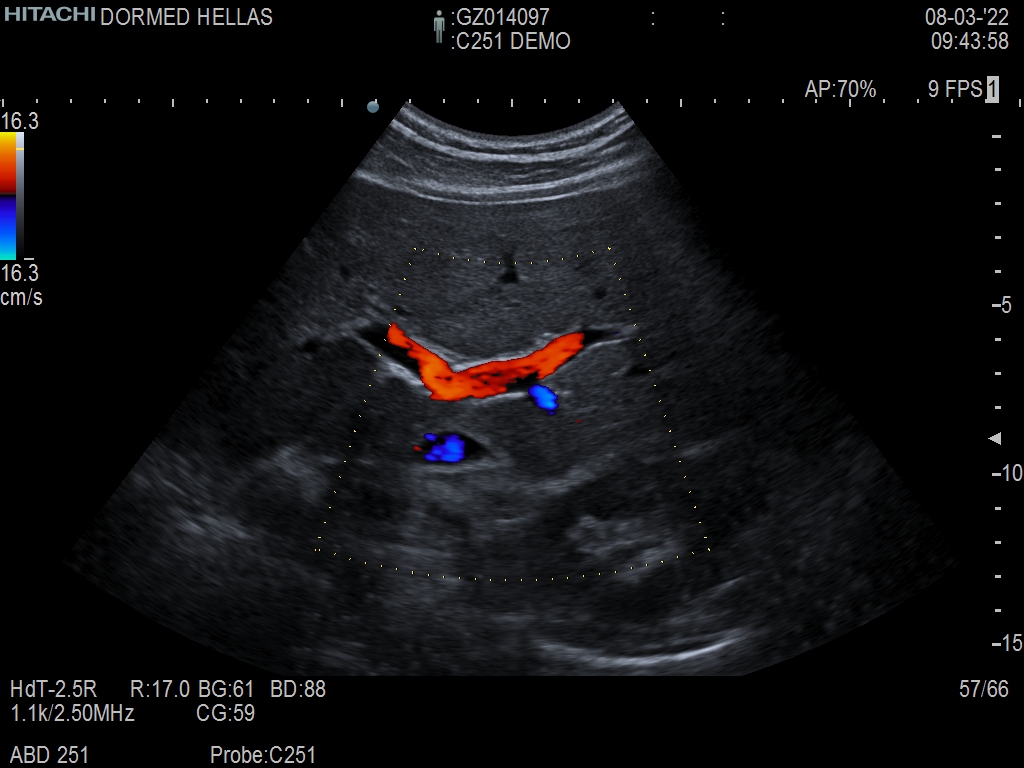

Hitachi C251 Ref Abdominal Convex – ARIETTA

ARIETTA Convex C251 Abdominal

Hitachi C251 Abdominal Convex – ARIETTA

Hitachi C251 Abdominal Convex – ARIETTA for Abdominal and Women’s Health

| Radiology functions | Contrast Harmonic Imaging (CHI), Elastography (RTE), RT Sonography (RVS) |